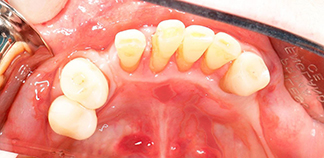

До лечения

Жалоба на отсутствие зубов длительное время.

Пациенту 63 года.

Как лечили

Из-за долго отсутствия нижних зубов и дефицита костной ткани удалены оставшиеся зубы. На нижнюю челюсть установлены четыре импланта и временная ортопедическая конструкция. В дальнейшем будет установлен постоянный протез.

Лечащий врач

БОЙКО Артемий Петрович